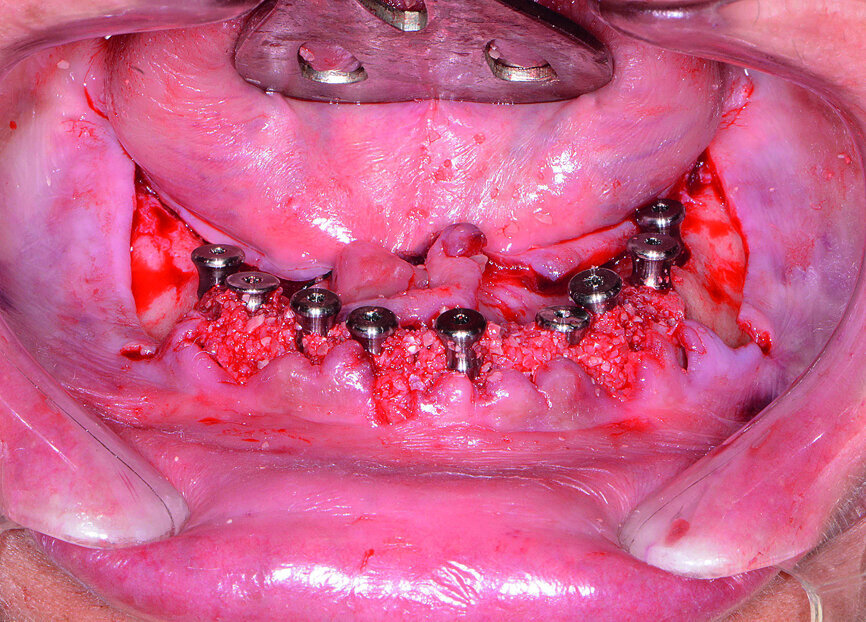

Fig. 15: Implants and healing caps with surrounding grafting.

Next, the patient’s untreatable mandibular teeth (Fig. 13) were extracted using the Physics Forceps (GoldenDent), a flap was reflected, and an alveoloplasty was performed. A bone-supported guide was seated in order to control the location and angulation of the implant osteotomies (Fig. 14). As the Hahn Tapered Implants were threaded into place, their deep, sharp threads engaged the walls of the socket sites and helped maintain proper position toward the lingual aspect. Because of anticipated tissue swelling as a result of the bone levelling procedure, 5 mm high healing abutments were connected to the implants in the lower arch (Fig. 15). The immediate dentures were soft-relined with Mucopren (Kettenbach) to seat over the Hahn Tapered Implant Healing Abutments, the hourglass shape and undercuts of which provided a degree of retention that enhanced dental function for the patient during healing (Fig. 16).